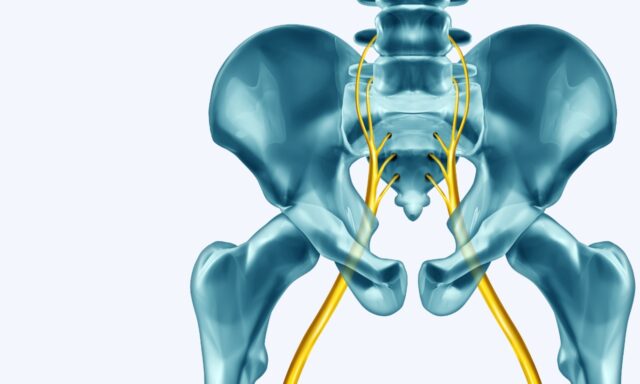

Lumbales radikuläres Syndrom

In dieser Folge sprechen wir mit Adam Dobson über alles, was mit dem lumbalen radikulären Syndrom zu tun hat - von seiner Definition der Erkrankung über den Ausschluss einer ernsthaften Pathologie bis hin zur Frage, wie er Patienten mit radikulärem Syndrom behandeln würde. Er berichtet auch von seinen persönlichen Erfahrungen mit dem lumbalen radikulären Syndrom.